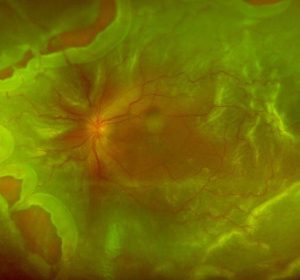

¿QUÉ ES LA DEGENERACIÓN MACULAR? La degeneración macular asociada a la edad (DMAE) es una enfermedad degenerativa que afecta a la mácula, parte de la retina en la que reside la visión central. La degeneración macular asociada a la edad provoca pérdida de la visión central y de detalle. Es una enfermedad que se manifiesta…